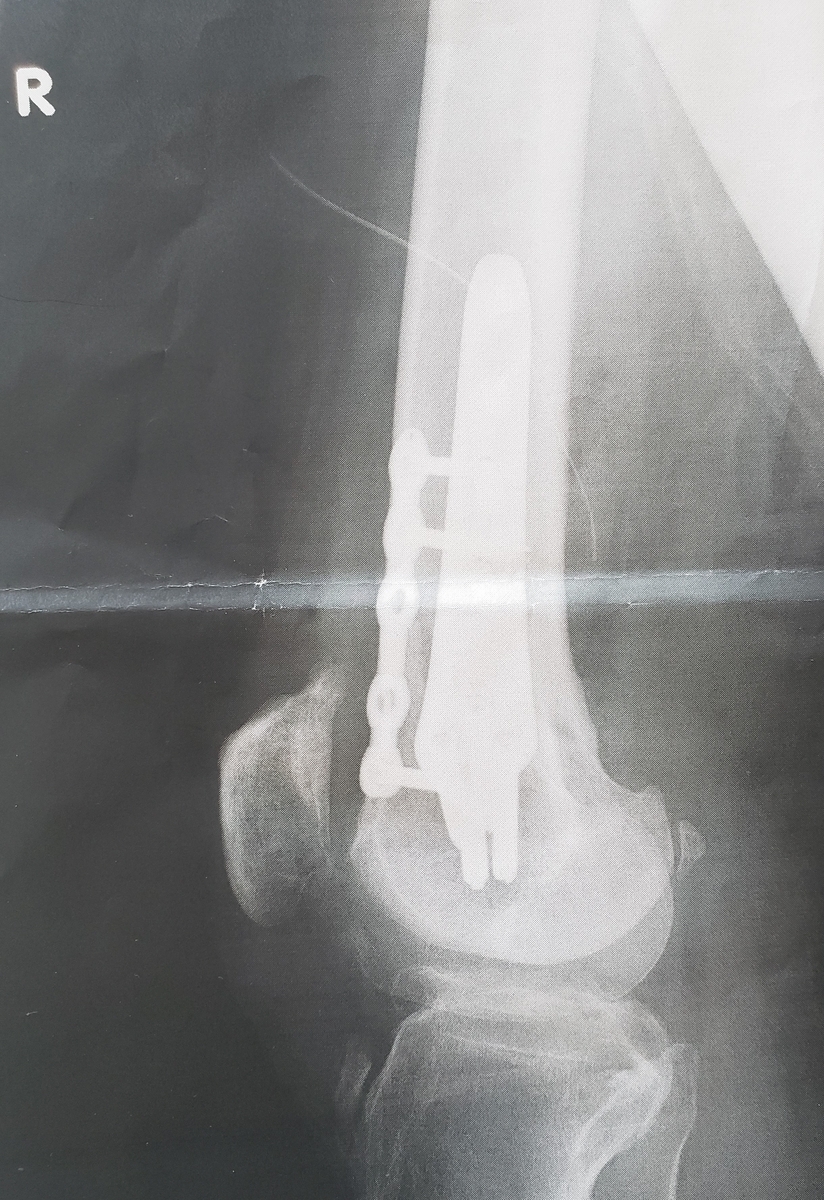

歩いてて突っ張った感じや、膝がぐらつく感じも、少しずつ解消されつつあるかなと。ま、手術から2か月経ちましたしね。